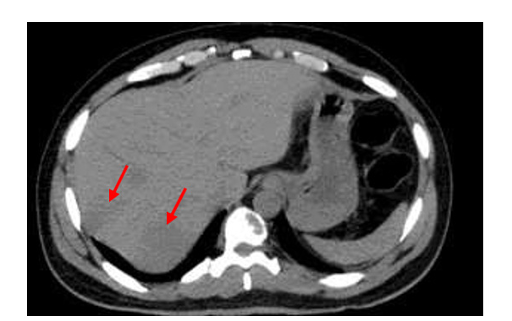

1. Abstract Metabolic dysfunction-associated fatty liver disease (MAFLD) is an escalating global health concern, impacting approximately 25-30% of the global population.